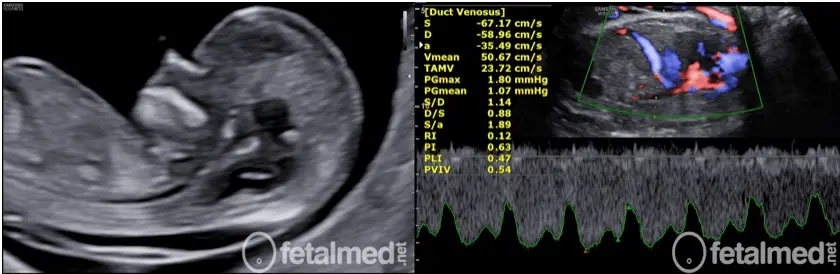

Comparação entre translucência nucal e Doppler do ducto venoso no exame morfológico de primeiro trimestre

A translucência nucal (esquerda) é realizada no exame básico. O Doppler do ducto venoso (direita) é feito apenas no exame morfológico de 1.º trimestre.

No exame morfológico de primeiro trimestre, além da TN, o médico avalia:

Ducto venosoAvalia a função cardíaca do bebê. Alterações no fluxo podem indicar cardiopatias ou síndromes cromossômicas.